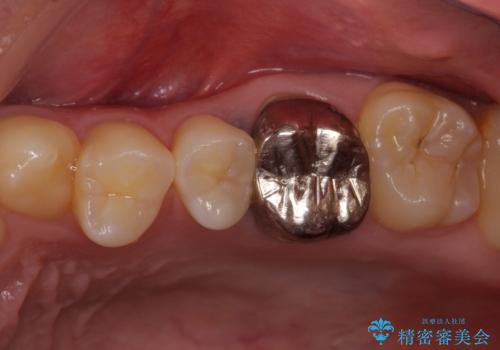

銀歯を白くしたい セラミックによる審美歯科治療

- 治療中の前歯と口腔内にある銀歯が気になるとのことで来院された患者様です。

土台に含まれている金属も含め、口腔内の金属は全て除去し、根管治療が必要な歯は根管治療を行い、オールセラミッククラウンやセラミックインレーにて治療することとしました。